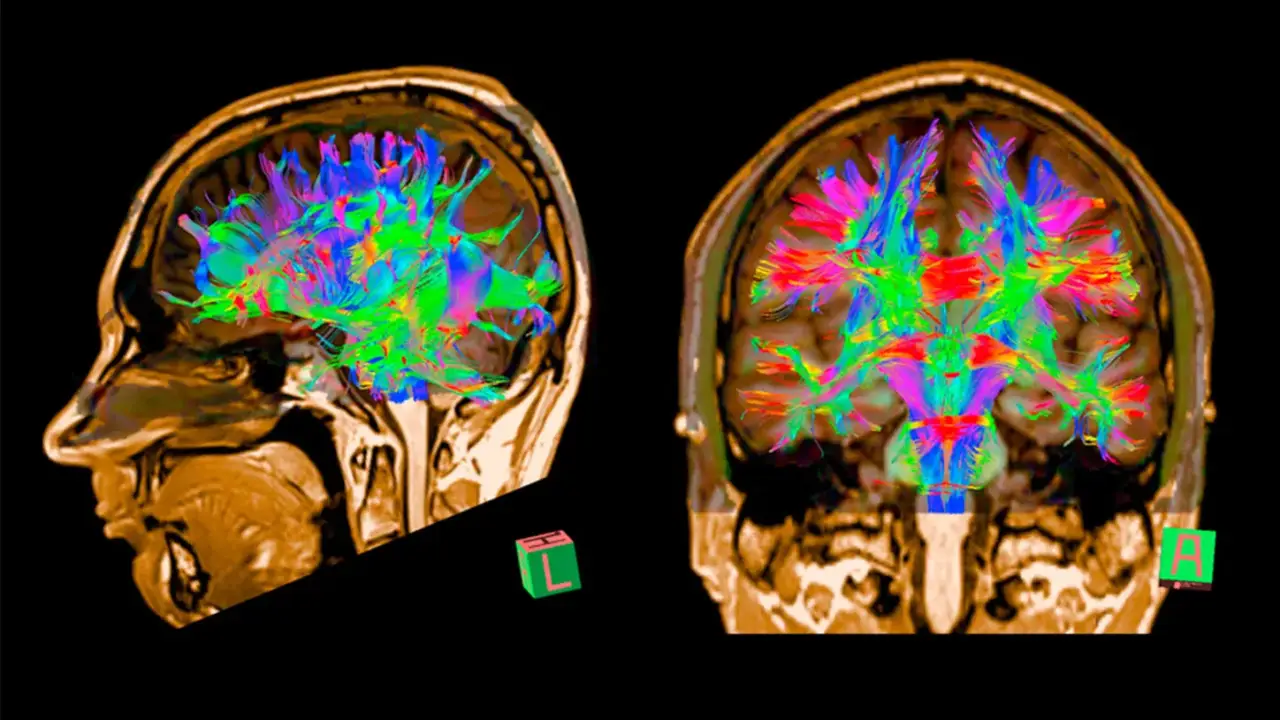

Kan testi pozitif çıktığında, beyin görüntüleme (PET veya MR) ile amiloid birikimi doğrulanabiliyor.